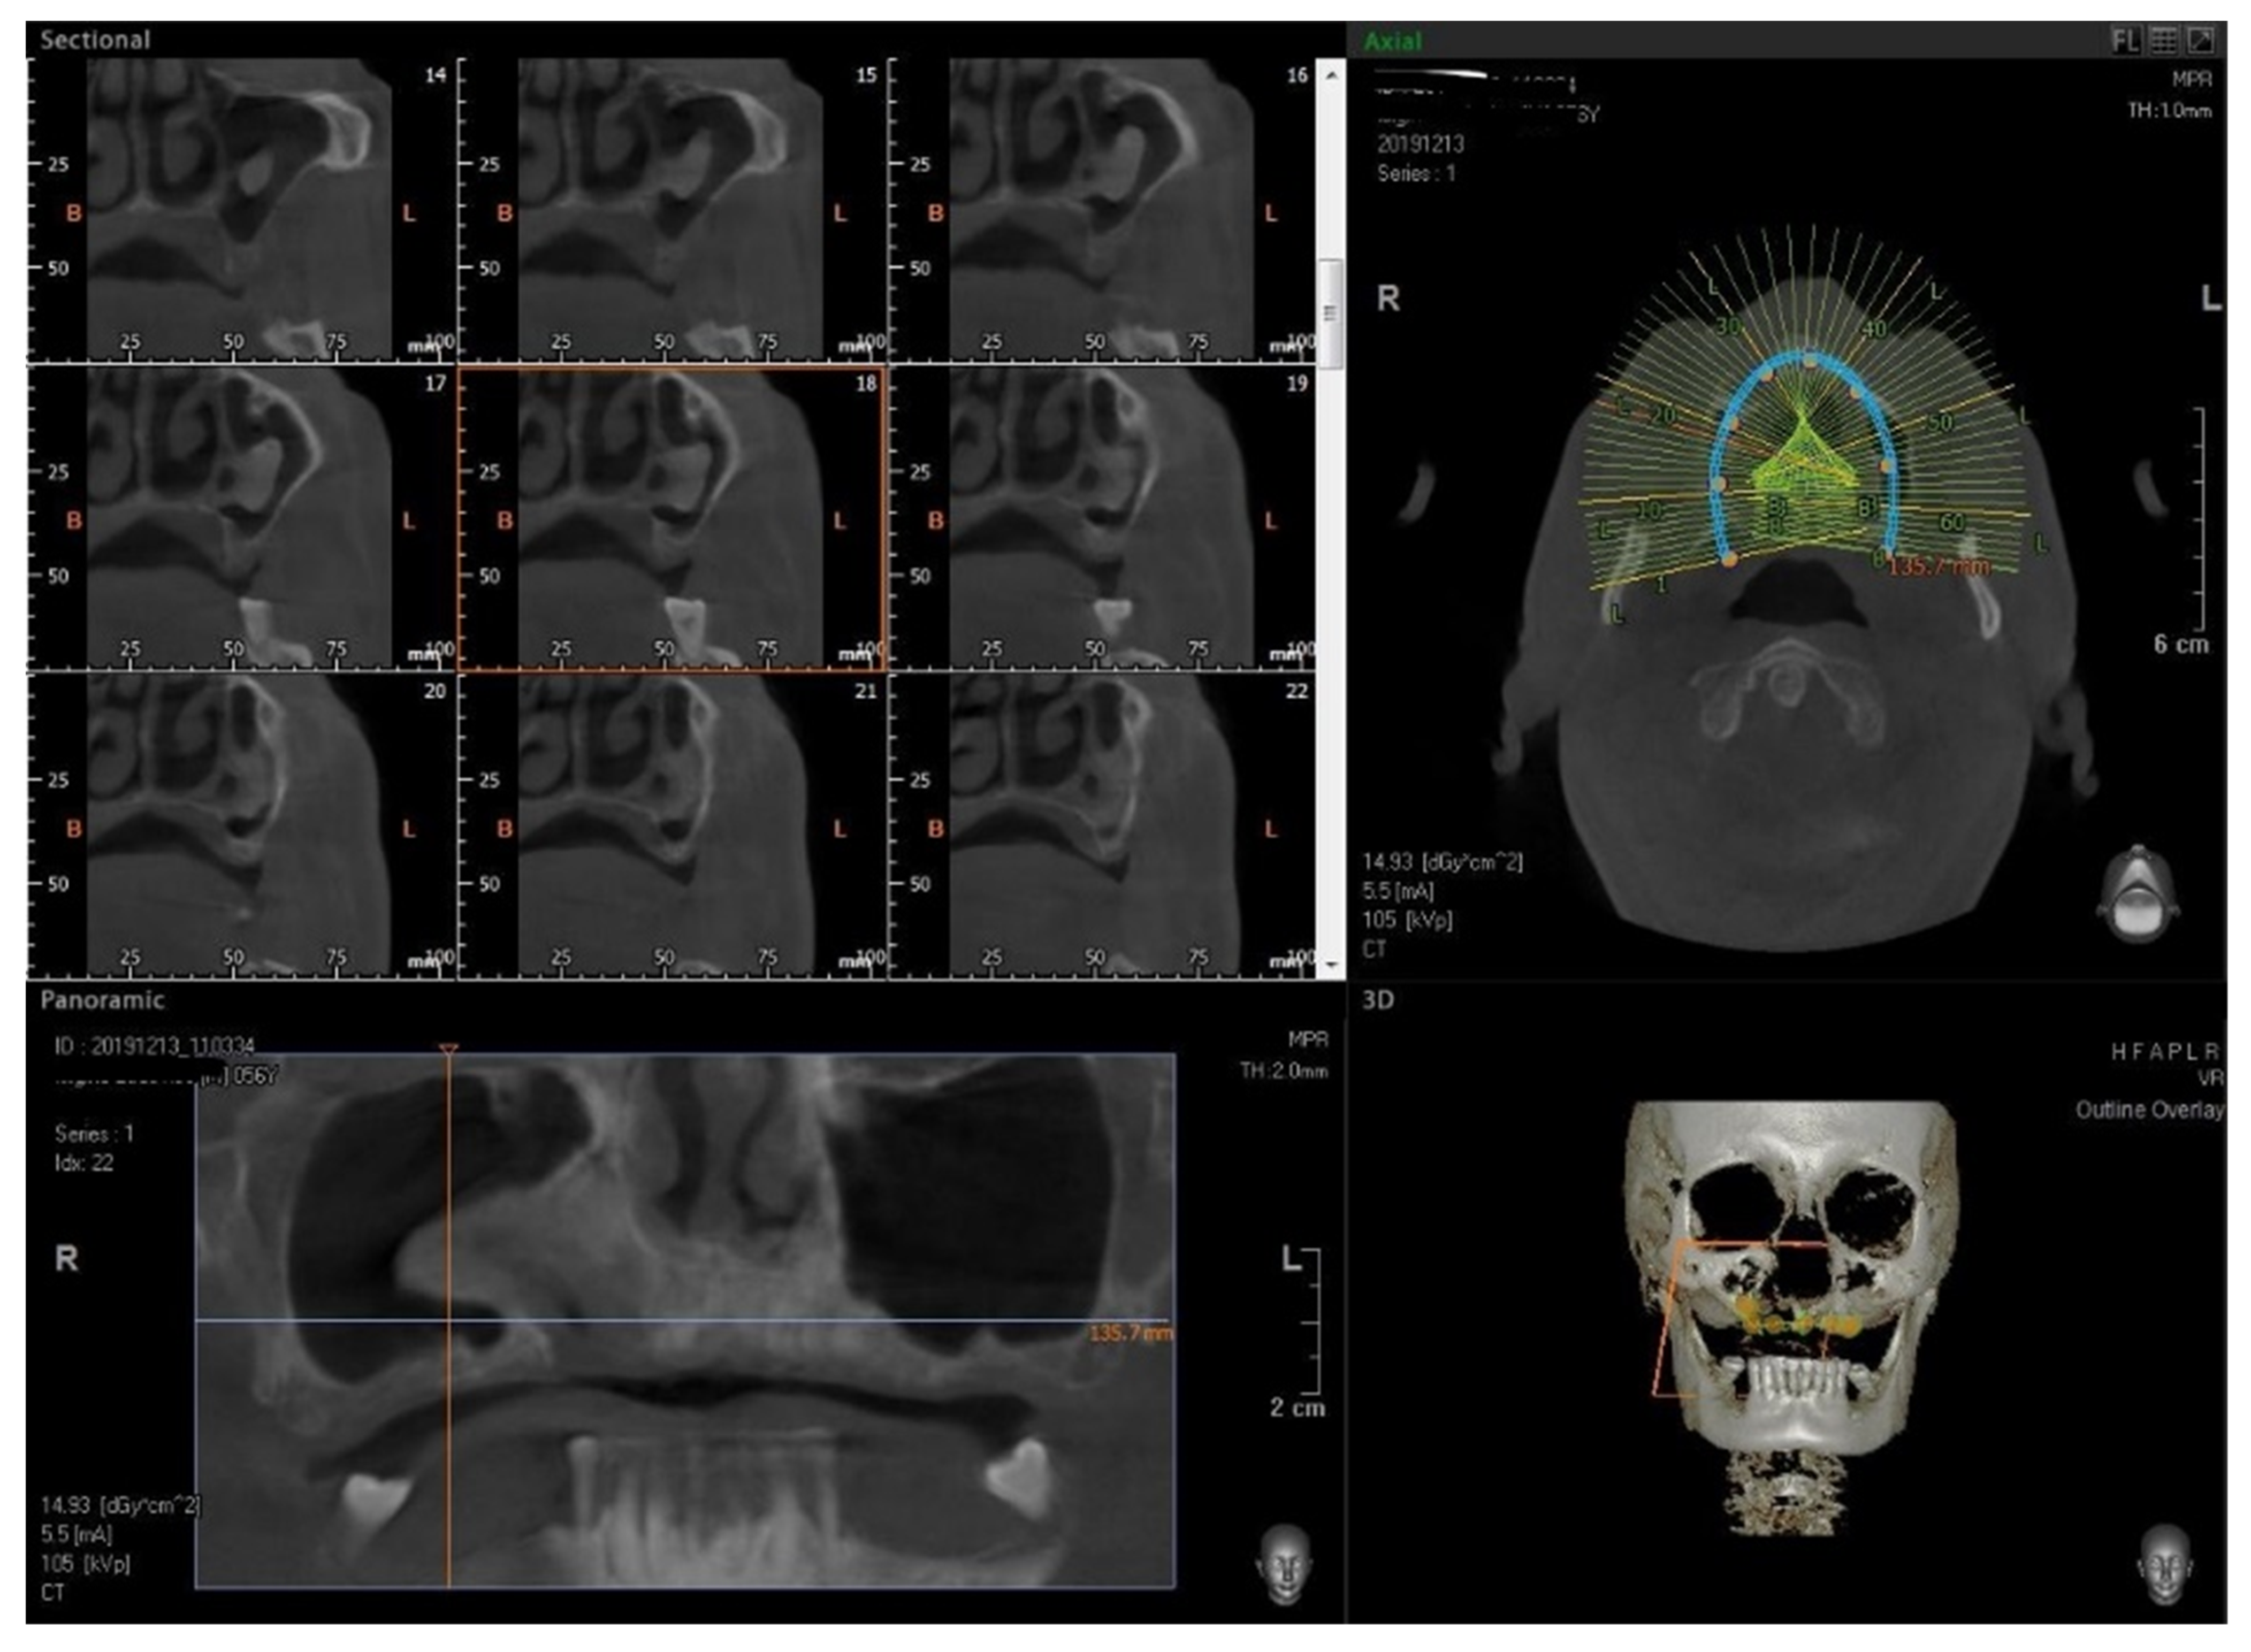

3.1. Surgical Procedure